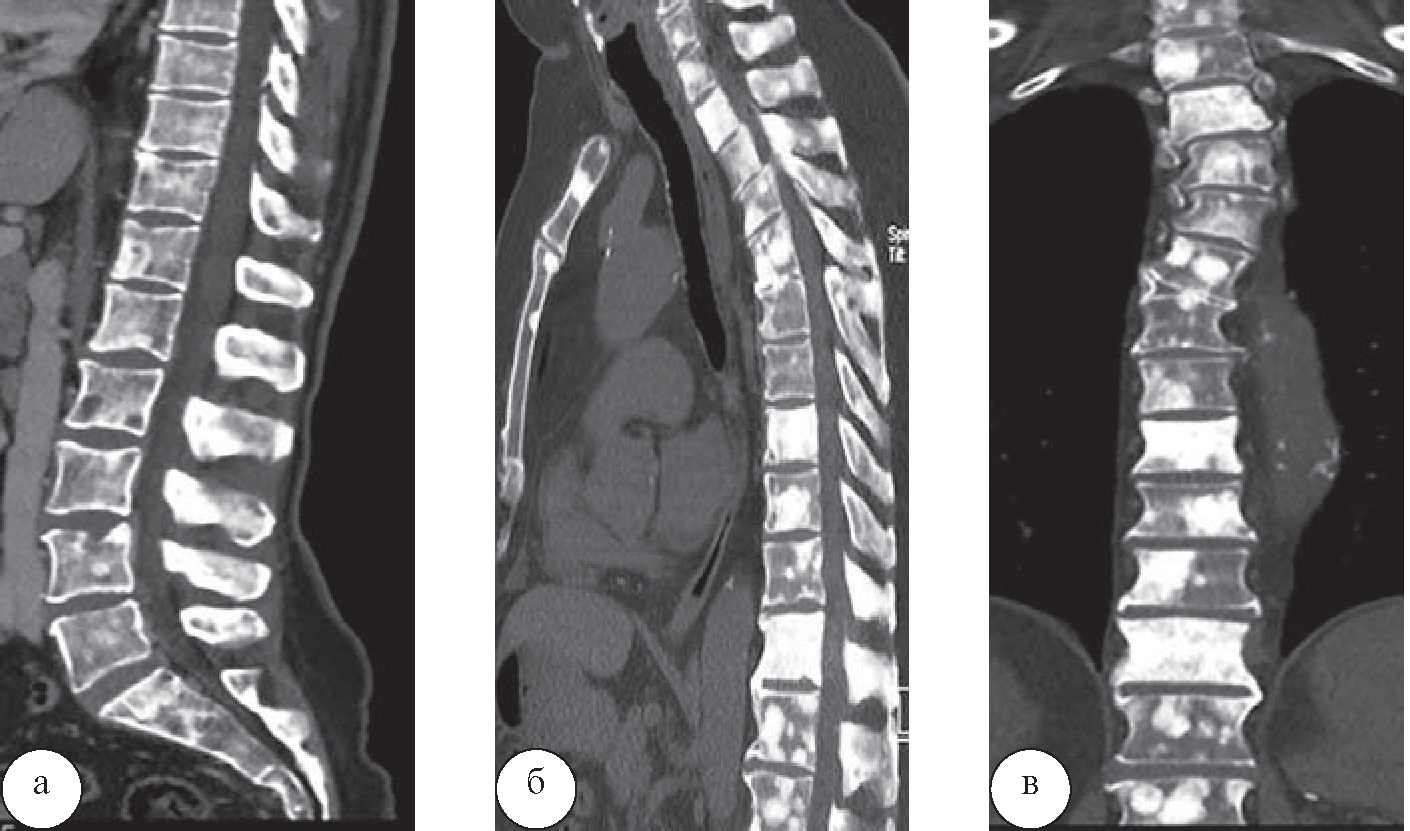

Ещё у одного пациента 67 лет в санаторной карте отсутствовало упоминание о раке предстательной железы в анамнезе, данные рентгенологического обследования представлены не были. Пациент был направлен на санаторное лечение в связи с выраженным болевым синдромом и диагнозом направления «остеохондроз позвоночника». Для уточнения причин болевого синдрома в санатории была выполнена КТ (рис. 8).

Рис. 8. Пациент Т., 67 лет. При КТ отмечаются множественные очаги уплотнения костной структуры в телах всех позвонков, остистых отростках, грудине и рёбрах. В анамнезе – брахитерапия по поводу рака предстательной железы, таким образом, данная картина соответствует остеобластическому метастатическому поражению скелета

По итогам КТ-обследования у данного пациента санаторное лечение было отменено в связи с наличием абсолютного противопоказания –множественных метастазов в кости. Таким образом, изменения программ лечебного воздействия в отношении всех пациентов были произведены после комплексного анализа данных КТ, МРТ, остеоденситометрии и рентгенографических исследований и получения дополнительной информации, отсутствовавшей в санаторных картах пациентов, заполненных на досанаторном этапе, вследствие детальной оценки дегенеративных изменений позвоночника. Наиболее значимую для врачей-специалистов санатория информацию дала КТ, поскольку при наличии протрузий и экструзий небольших размеров основными факторами, влияющими на выбор методик лечебного воздействия, служили изменения именно костных структур. Дополнительная информация, полученная при МРТ, имела значение в тех случаях, когда требовалось оценить степень сдавления нервных корешков либо спинного мозга, в то время как при КТ это не представлялось возможным. Однако результаты МРТ при этом значимо не повлияли на изменения программ лечения, запланированных в соответствии с результатами КТ, а явились дополнительным фактором, подтверждающим назначение или исключение конкретных методик лечебного воздействия из программы.